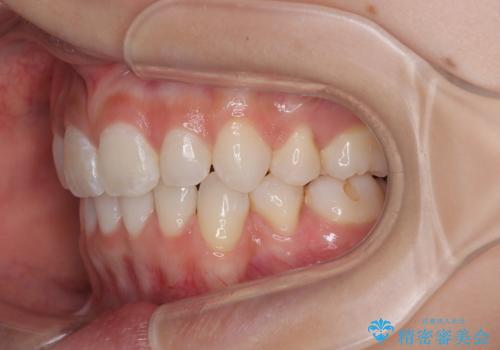

- 口を閉じたときに飛び出してしまう上顎前歯を気にして来院された患者様です。

下顎はデコボコが気になっていたため、上下左右第一小臼歯4本を抜去して、ワイヤー装置にて口元の突出感を改善するよう矯正治療を行うこととしました。

下唇に前歯が当たって跡が残ってしまう状態でしたが、スッキリとした口元に仕上げることができました。